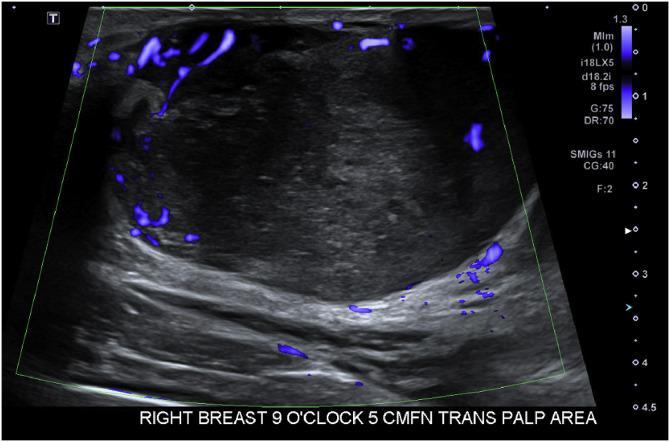

一名15岁女孩患乳腺高级别梭形细胞化生癌。

High-grade spindle cell metaplastic carcinoma of the breast in a 15-year-old girl.

Metaplastic breast cancer in pediatric patients is exceedingly rare with only occasional case reports to present imaging and guide management. Typically diagnosed in patients over 50 years old, metaplastic carcinoma is an aggressive type of breast cancer representing less than 1% of all breast cancers in the United States. To our knowledge, we describe the youngest person to be diagnosed with metaplastic breast cancer in the US. This case underscores the need for clinical vigilance in evaluating rapidly growing breast masses in adolescents. It also emphasizes the value of histopathologic confirmation, even when imaging findings suggest a benign process, to ensure timely diagnosis and management.

小儿患者的化生性乳腺癌极为罕见,仅有零星病例报告用于呈现影像学表现并指导治疗。化生性癌通常在50岁以上的患者中被诊断出来,是一种侵袭性乳腺癌类型,在美国所有乳腺癌中所占比例不到1%。据我们所知,我们描述了美国最年轻的被诊断为化生性乳腺癌的患者。该病例强调了在评估青少年快速生长的乳腺肿块时保持临床警惕的必要性。它还强调了组织病理学确诊的价值,即使影像学表现提示为良性病变,以确保及时诊断和治疗。